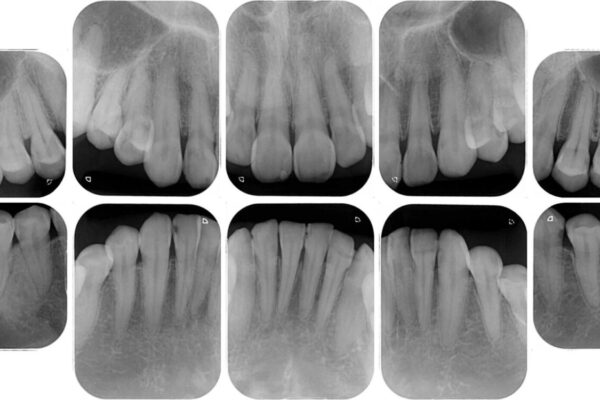

上下前歯や奥歯の虫歯治療を希望して来院された患者様です。

全顎的にむし歯が多く、根管治療の必要な奥歯や、審美的に気になっている前歯を中心にオールセラミッククラウンにて補綴治療を行うこととしました。

上顎前歯は歯肉退縮により歯根が露出していたため、事前に歯肉移植術により根面被覆を行い、その後にオールセラミッククラウンを装着することとしました。

治療前

• むし歯だらけの前歯をオールセラミッククラウンできれいに 治療前画像